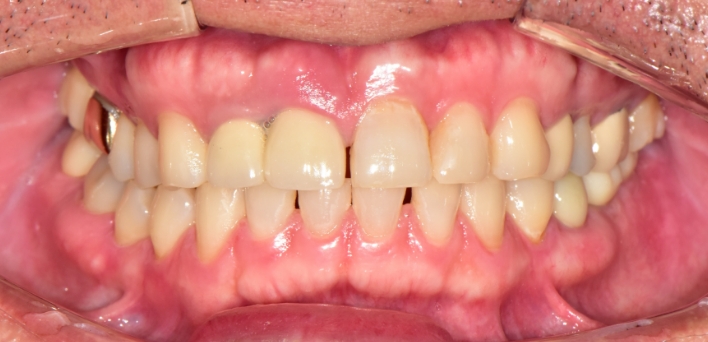

임플란트 : 손 ** 님 (50대)

치아가 있다는게, 아직도 정말 꿈만 같아요.

Before Before

After After

환자 특징

환자 특징01무치악 상태

환자 특징02수년간 무치악으로 지내심

임플란트가 불가능할것이라

생각하고 내원

위, 아래 6개씩 식립

디지털 풀아치 임플란트